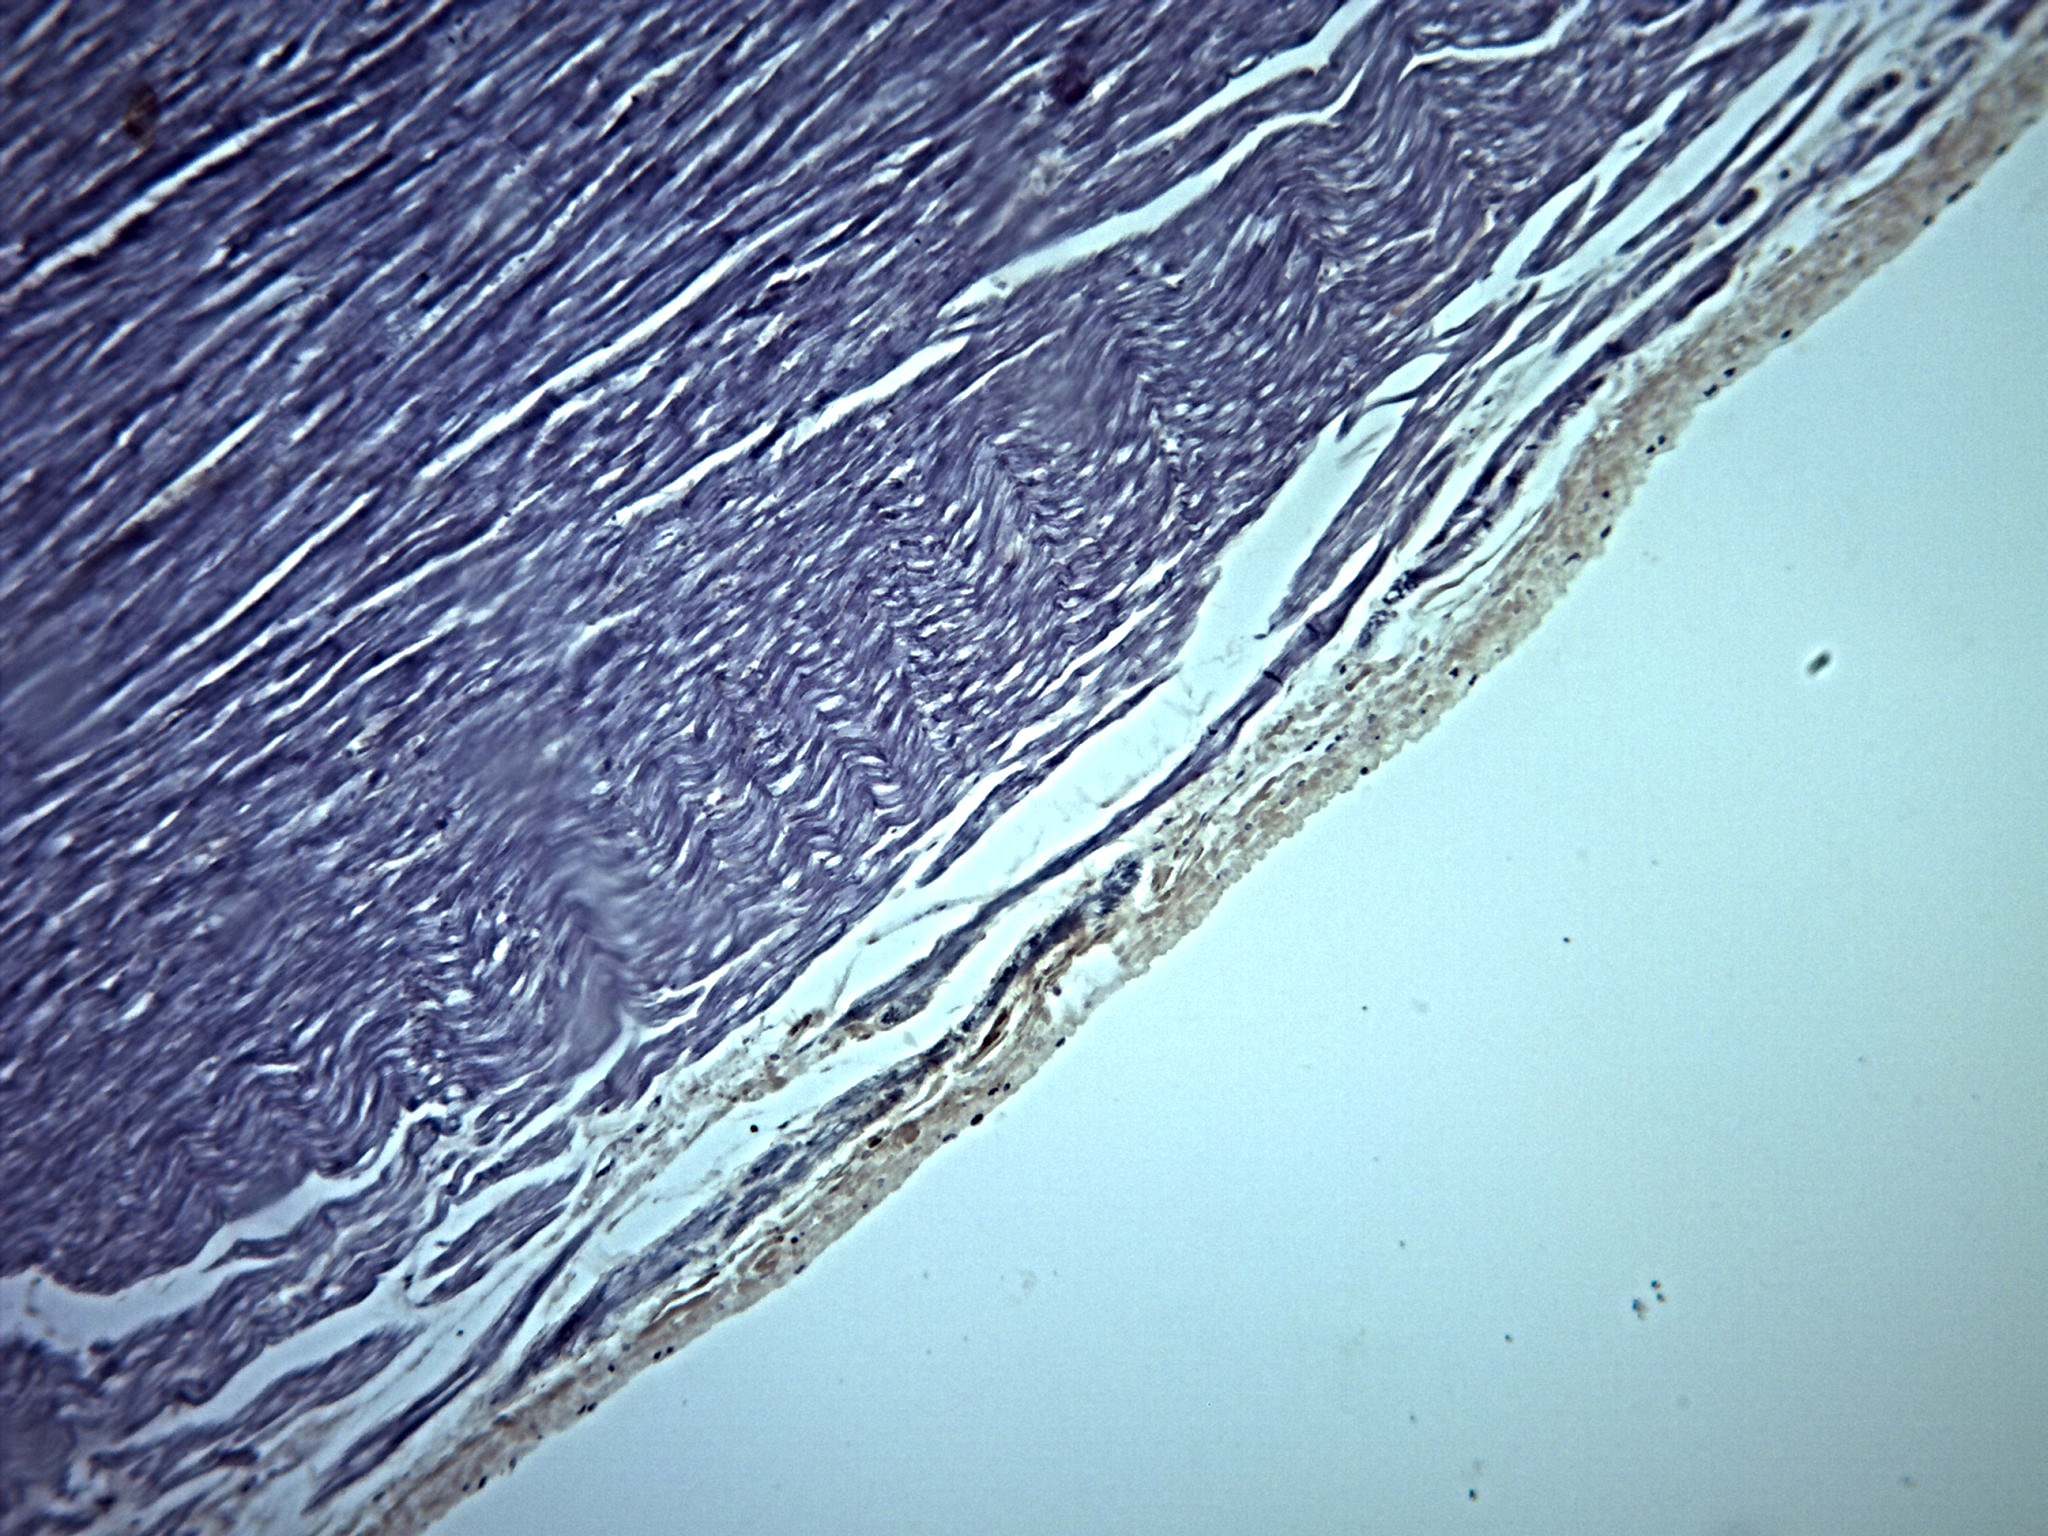

• Sistema Circulatório

Sistema Circulatório